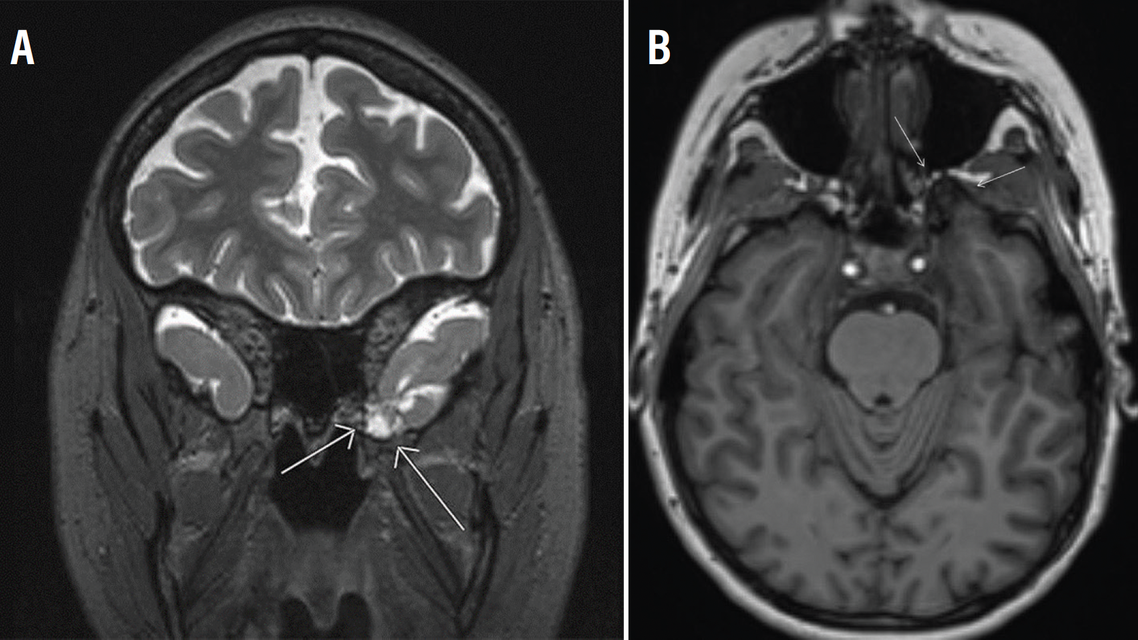

A 3T epilepsy-protocol MRI, including thin-slice T1-weighted, T2-weighted, fluid-attenuated inversion recovery, diffusion-weighted, and susceptibility-weighted imaging, showed a dysplastic anterior temporal pole vs cystic encephalomalacia extending into a sphenoid bone defect along the left cranial fossa, consistent with an encephalocele (Figure). WX was scheduled for epilepsy monitoring unit admission. However, the day before the scheduled admission, WX developed bilateral peripheral vision loss and new bitemporal headaches with associated tinnitus and a positional component as well as clear rhinorrhea. WX was admitted to the general neurology service.

Figure. Left anterior temporal encephalocele: axial (A) and coronal (B) views.